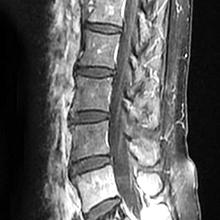

30多年來,惡性腫瘤一直高居我國10大死因首位。隨著治療的進步,罹患癌症的病人存活時間越來越長。然而,隨著存活時間延長,惡性腫瘤發生轉移的機會也會提高,在惡性腫瘤病人中,癌細胞轉移至骨頭的機會僅次於肺臟和肝臟,而在所有的骨轉移腫瘤中,又以轉移到脊椎最為常見。